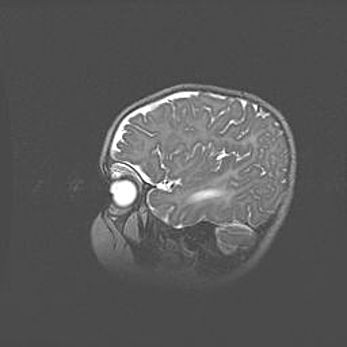

Аномалия Денди-Уокера. Признаки гипоплазии мозолистого тела.

Возраст: 5 месяцев 3 дня

Вес: 5550 г

Пол: мужской

Окружность головы: 39 см

Срок гестации: 40 недель

Аномалия Денди-Уокера – это порок развития головного мозга, для которого характерна триада симптомов: гипотрофия или аплазия червя мозжечка и/или полушарий мозжечка, расширение четвёртого желудочка с формированием ликворной кисты задней черепной ямки, гипертензионная гидроцефалия различной степени.

Гипоплазия мозолистого тела относится к дефектам внутриутробного этапа развития мозговой ткани, возникающим в процессе закладки структур головного мозга, что происходит на начальных этапах развития эмбриона.